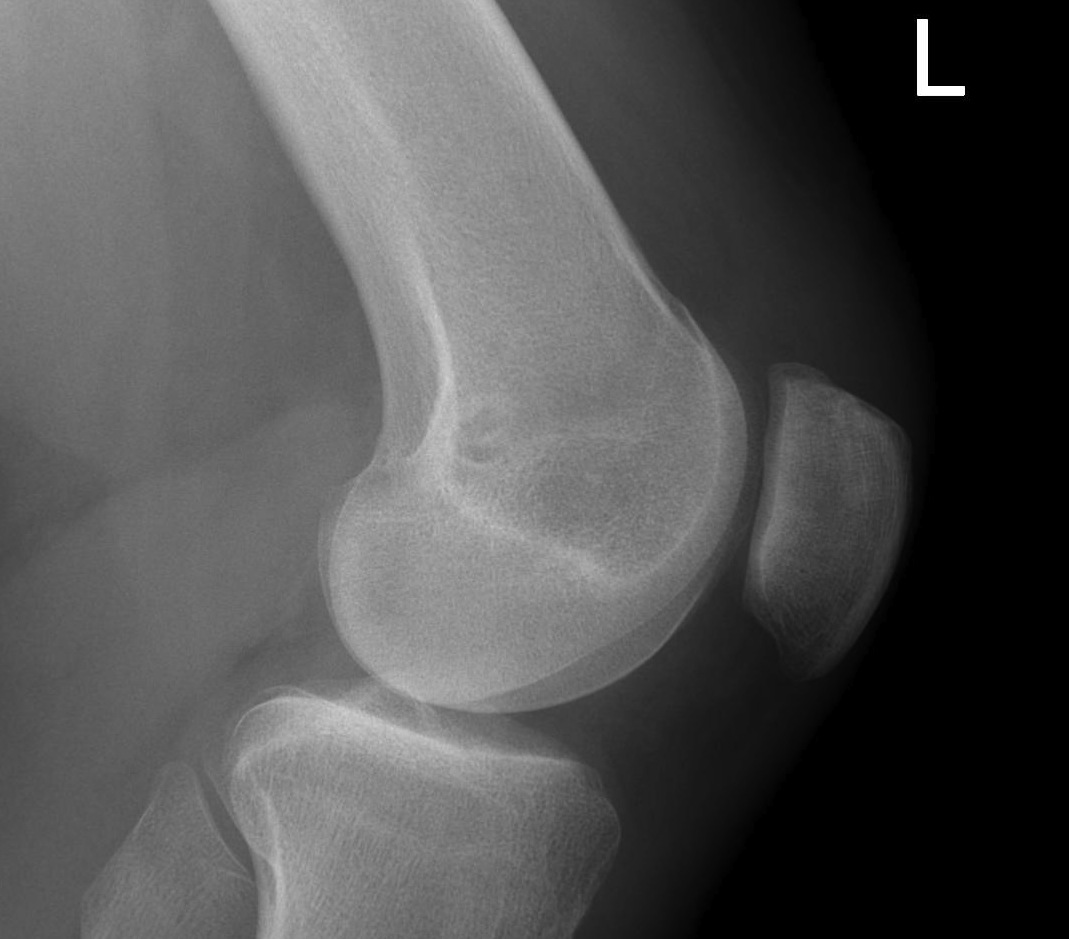

2. Assess Trochlea Dysplasia

Dejour Crossover Sign

- lateral x-ray at 30o with condyles superimposed

- identify base of trochlea

Normal

- clearly defined trochlea groove

Abnormal / Crossover

- line of floor of trochlea crosses lateral lip of condyle

- indicates trochlea is deficient proximally

Trochlea depth

- < 8 mm shallow

Dejour grading system 1 - IV